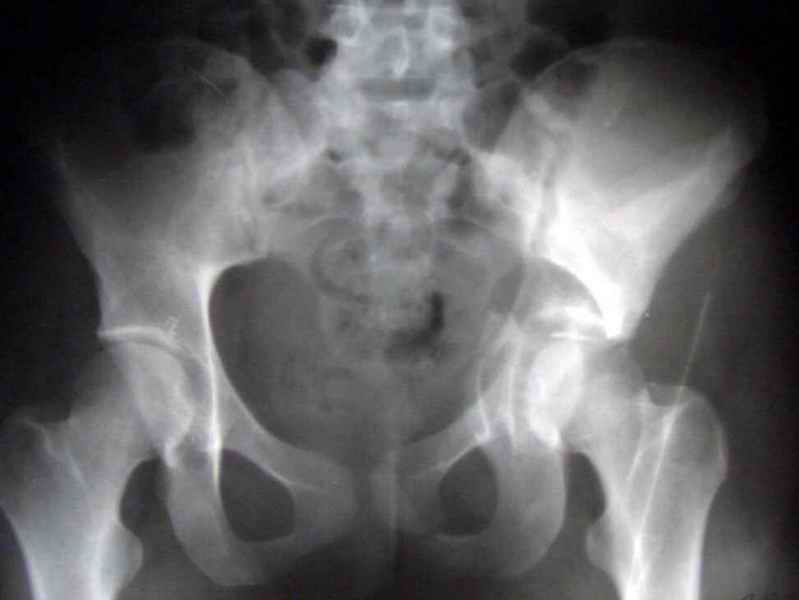

Посылаю схемы и 3D реконструкцию подобного повреждения. Называется он полным высоким двухколонным переломом вертлужной впадины, а "переломы крыла и тела подвздошной кости" входят в это понятие.

Вариантов остеосинтеза много (можно и не оперировть, т.к. конгруентность при таких переломах как правило сохраняется)